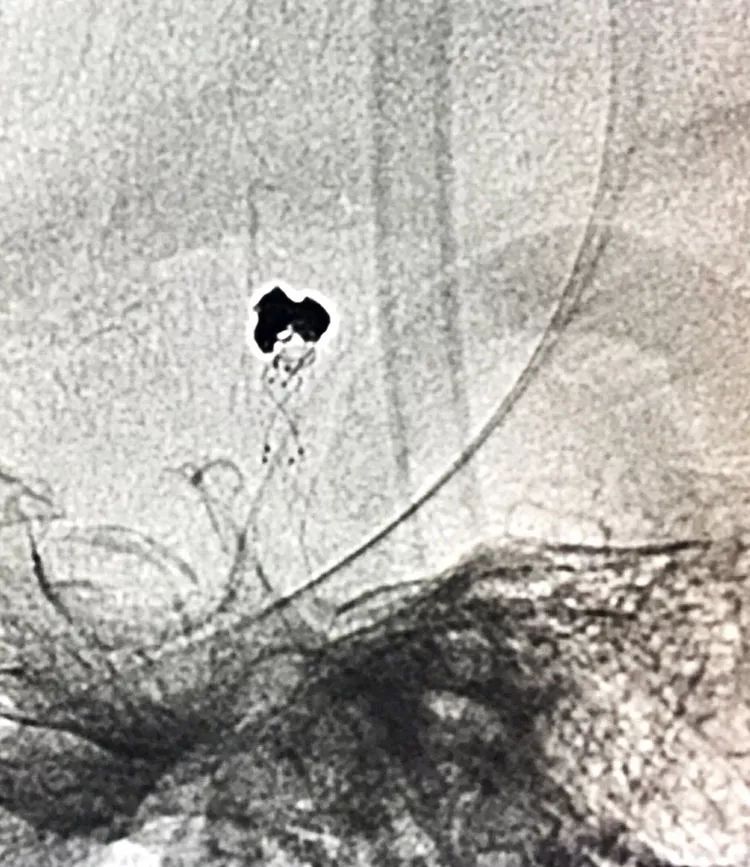

换用一根新的Echelon10微导管,头端塑成C型,以Arvigo14微导丝引导(先前的Sychro14微导丝的头端已经有损了),经LVIS支架内部接近瘤腔后部的死腔,但微导丝可以进入死腔,微导管头死活钻不进去,被LVIS支架的网丝挡住去路,怎么办?那就隔着渔网袜挠痒!

微导管头顶在支架网眼处,投送一枚1.5-2的小圈,一开始弹簧圈走行入载瘤动脉(支架)内,用扭具调整弹簧圈头端的行进方向,并随之微调微导管头的方向和张力,圈终于成功钻入死腔!

再投入一枚1.5-3的小圈

继续钻入一枚1.5-2的小圈

嗯,完美收官!